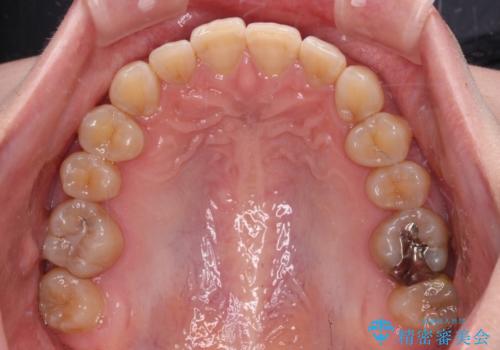

- 下顎の八重歯を気にして来院された患者様です。

マウスピース矯正でもワイヤー矯正でも対応可能であり、マウスピースによる治療を希望されたため、インビザラインを用いることとしました。

下顎前歯にデコボコが集中していたため、顎間ゴムによる後方移動とIPR(歯と歯の間を削ること)により歯列を整えることとしました。

下顎前歯のデコボコが集中しており、奥歯の咬み合わせは、上顎に対して下顎が前方位にある状態でした。下顎の歯列を後方へ移動させる治療はインビザラインの得意とするところですので、1年程度で無事に治療を終えることができました。